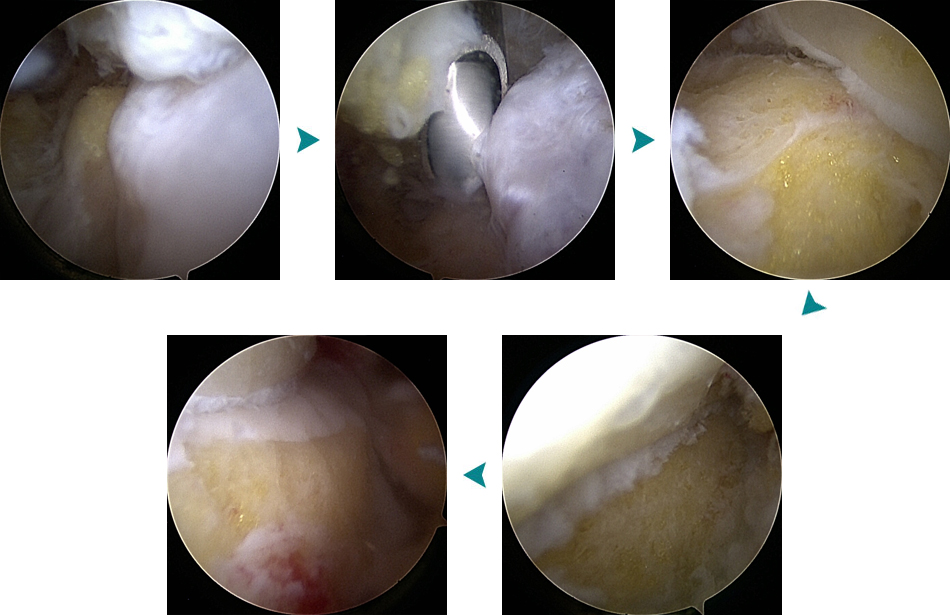

관절경 수술 - 전방 골극 제거 및 손상된 연부조직 절제 등

발목 전방충돌증후군

관절경하 골극절제술